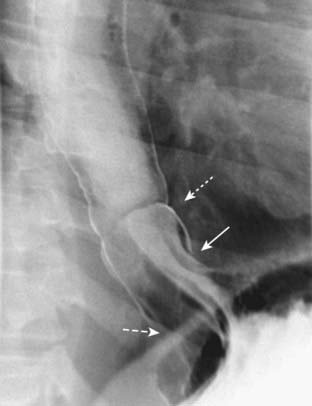

Figure 18-5 Sliding hiatal hernia.

There is a bulbous collection of contrast representing the stomach herniated above the diaphragm. There are gastric folds present in the hernia, identifying it as part of the stomach (solid white arrow). Notice the esophagus does not narrow as it normally does when passing through the esophageal hiatus (dashed white arrow). Just above the hernia is a thin, weblike filling defect characteristic of a Schatzki ring (dotted white arrow). The Schatzki ring marks the level of the esophagogastric junction.

imageThe radiologic findings of hiatal hernia include a bulbous area of the distal esophagus containing oral contrast at the level of the diaphragm with failure of the esophagus to narrow on multiple images as it passes through the esophageal hiatus, extension of multiple gastric folds above the diaphragm, and sometimes visualization of a thin, circumferential filling defect in the distal esophagus called a Schatzki ring.

A Schatzki ring marks the position of the esophagogastric junction so that its appearance above the diaphragm indicates the presence of a sliding hiatal hernia (Fig. 18-5).